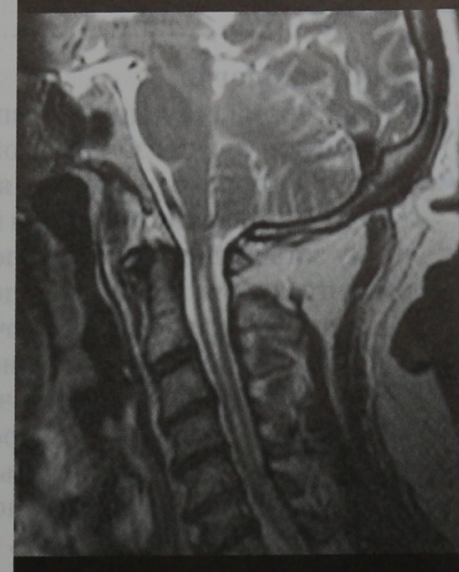

Аномалия Арнольда-Киари: MRI снимки